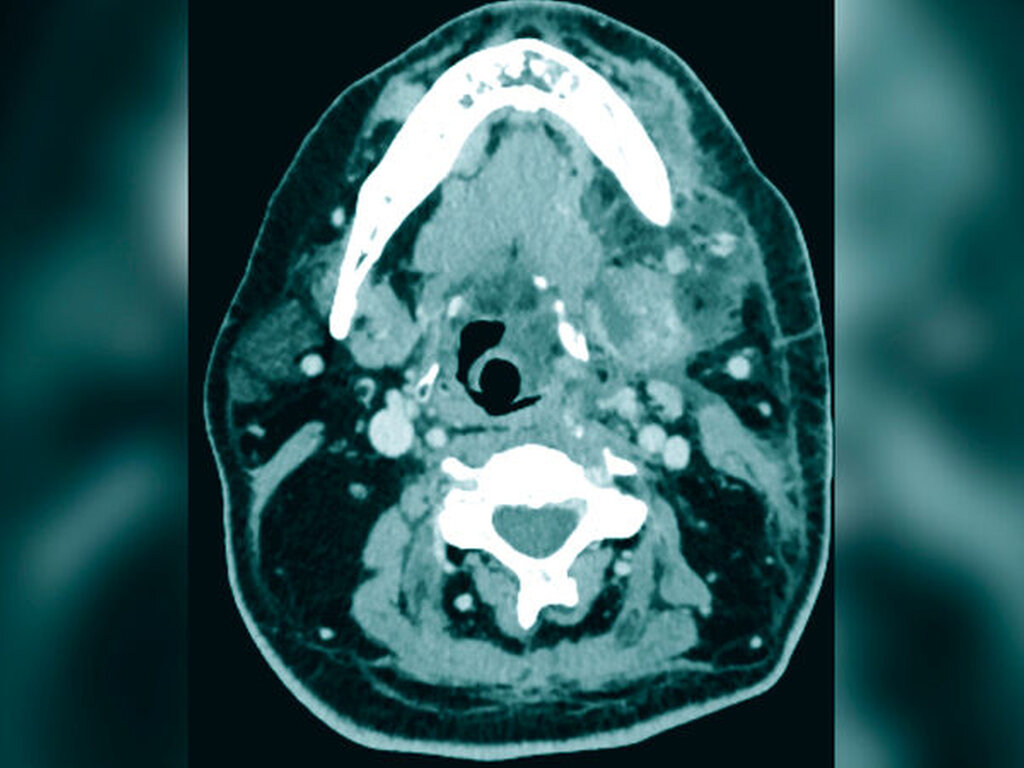

Es bestand die Indikation zur notfallmäßigen chirurgischen Intervention mittels Abszessdrainage. Hierzu erfolgten zunächst die Eröffnung der submandibulären und der perimandibulären Kompartimente über eine extraorale Schnittführung sowie die Extraktion des Zahnes 36. Darüber hinaus wurden die zervikalen und die jugulären Muskelfaszien zur weiteren Entlastung des entzündlichen Geschehens eröffnet. Bei der Drainage zeigte sich neben dem erwarteten Pus- und Blutabgang auch der Abgang von nekrotisch verändertem Muskelgewebe und gebildetem Gas nahezu im gesamten Halsbereich (Abbildung 3). Nach dem Debridement wurde der Wundbereich großzügig gespült. Abschließend wurden multiple Drainagen in die eröffneten Logen eingebracht und mittels Annaht fixiert (Abbildung 4).

Im initialen Stadium ist eine rasche Diagnosefindung entscheidend für die Prognose der Patienten. Eine erweiterte Diagnostik mittels Computertomografie ist schnellstmöglich anzustreben. Die radiologische Symptomatik zeigt neben Abszessformationen – wie im vorgestellten Fall – vor allem Lufteinschlüsse und Einschmelzungen mit Flüssigkeitsansammlungen in den tieferen Faszienanteilen. Das umgebende Fettgewebe und die umgebende Muskulatur stellen sich oftmals verdickt dar [Fais et al., 2018]. Obgleich diese radiologischen Phänomene pathognomonisch für die Erkrankung sind, finden sie sich nicht in allen Patienten. Eine chirurgische Exploration führt in der Regel zur Diagnose. Bei Eröffnung der Kompartimente lassen sich neben Pus und Blut auch nekrotische Muskulatur und subkutanes Gewebe darstellen.